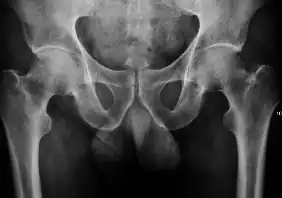

Projectional radiography ("X-ray") is the first imaging technique of choice in hip pain, not only in older people with suspected osteoarthritis but also in young people without any such suspicion. In this case plain radiography allows categorization as normal hip or dysplastic hip, or with impingement signs, pincer, cam, or a combination of both.[1]

X-Ray

Projectional radiography ("X-ray") is currently useful not only in older people in whom osteoarthritis of the hip is suspected but also in younger people without osteoarthritis, who are being evaluated for femoroacetabular impingement (FAI) or hip dysplasia.[1]

Plain radiography allows us to categorize the hip as normal or dysplastic or with impingement signs (pincer, cam, or a combination of both). Besides these, pathologic processes like osteoarthritis, inflammatory diseases, infection, or tumors can also be identified (Figure 1).[1]

- Osteoarthritis

In adults, one of the main indications for radiographs is the detection of osteoarthritic changes (Figure 1(e)). Nevertheless, radiographs usually detect advanced osteoarthritis that can be graded according to the Tönnis classifications. The grading system ranges from 0 to 3, where 0 shows no sign of osteoarthritis. Intermediate grade 1 shows mild sclerosis of the head and acetabulum, slight joint space narrowing, and marginal osteophyte lipping. Grade 2 presents with small cysts in the femoral head or acetabulum, moderate joint space narrowing, and moderate loss of sphericity of the femoral head. Grade 3 is the severest form of osteoarthritis, which manifests as severe narrowing of the joint space, large subchondral cyst with productive bone changes that may lead to deformity of the bone components of the joint, while secondary osteoarthritis due to calcium pyrophosphate deposition can be diagnosed when calcification of hyaline cartilage and fibrocartilage is detected.[1]

There are other pathological conditions that can affect the hip joint and radiographs help to make the appropriate diagnosis. Acute bacterial septic arthritis can be diagnosed by radiographs when a fast regional osteoporosis and destructive monoarticular process develops (Figure 1(f)). In case of tuberculous or brucella arthritis it is manifested as a slow progressive process, and diagnosis may be delayed.[1]